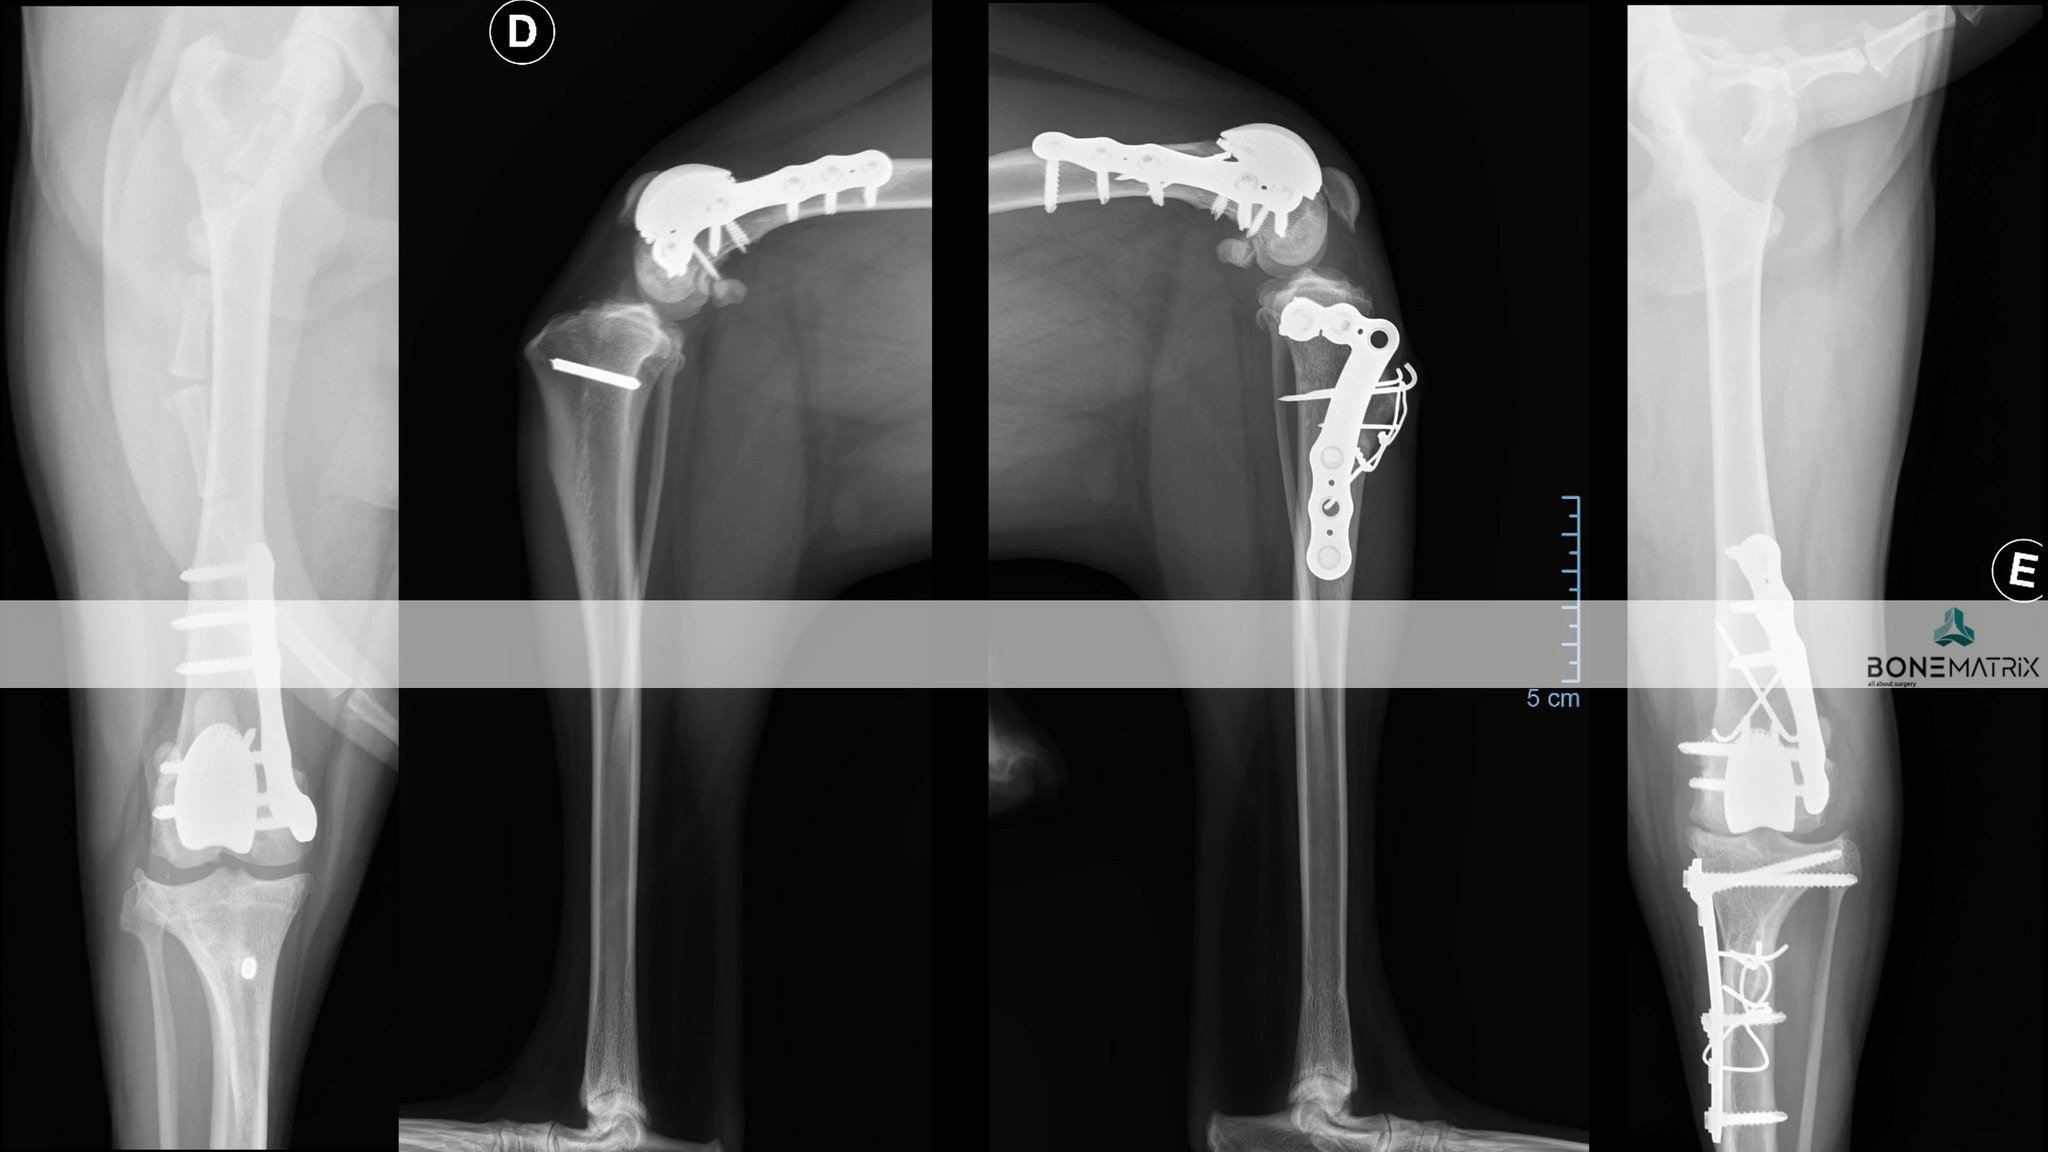

Caso complexo mas onde tudo acabou bem.

Right side.... DFO (varus, torsion correction), PGR, TTTT (torsion correction)

Left side... DFO (varus and torsion correction, shortening), PGR, CWTO (torsion correction, TPA correction, patella distalization), TTT (patela distalization)